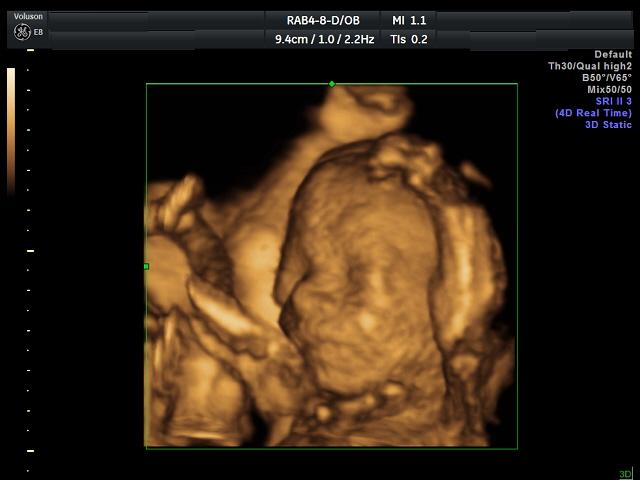

Ahojky byli jsme v nemocnici.........